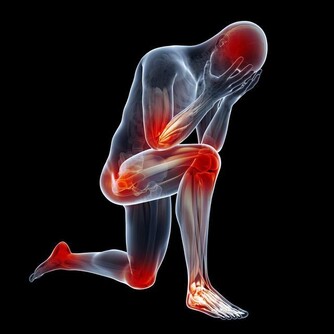

❸ 腰疼腿也疼

想減少腰病的風險,試試做這些吧

腰部神經受到壓迫時,不良狀態會從腰部開始,放射到整個下肢,造成下肢無力、雙腳麻木、不能踮腳走路等情況出現,這種狀況也需要及時求助醫生。